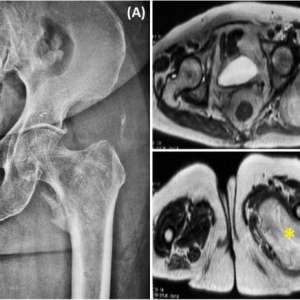

Образование в ягодичной области у пациента с множественной миеломой

Женщина, 78 лет

В анамнезе множественная миелома и AL-амилоидоз. В 2022 году проведен курс лечения бортезомибом, леналидомидом и дексаметазоном (VRD), отмечен полный ответа на лечение.

Жалобы на появление образования в ягодичной области, пациентка отмечает быстрый рост образования за 2 месяца. Она регулярно наблюдается в гематологическом отделении и амбулаторной клинике и в настоящий момент не получает поддерживающую терапию.